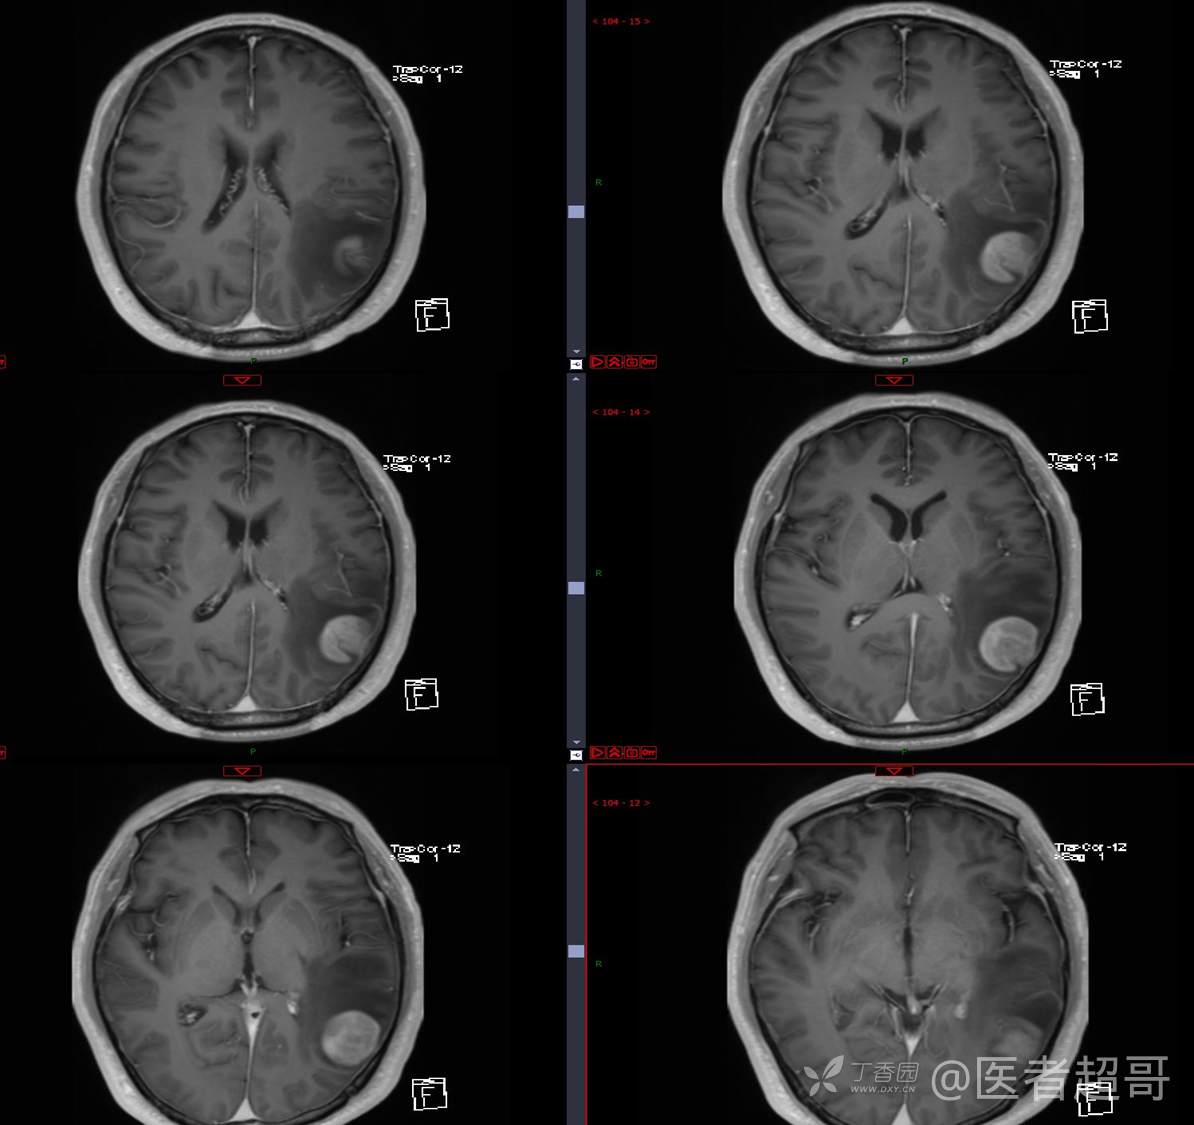

比较典型病例,CT、MRI齐全,请分析,领丁当!

男,56岁

主 诉:查体发现颅内占位10天。

现病史:患者于约10天前于我院查体时行颅脑MRI提示左侧顶叶占位病变,无头痛头晕,无恶心呕杜,无肢体活动不利,无感觉异常,现患者为求进一步治疗,就诊于我科门诊,门诊以“颅内占位性病变”收入我科。患者自发病以来,神志清,精神可,饮食及睡眠差,大小便无明显异常,体重无明显变化。